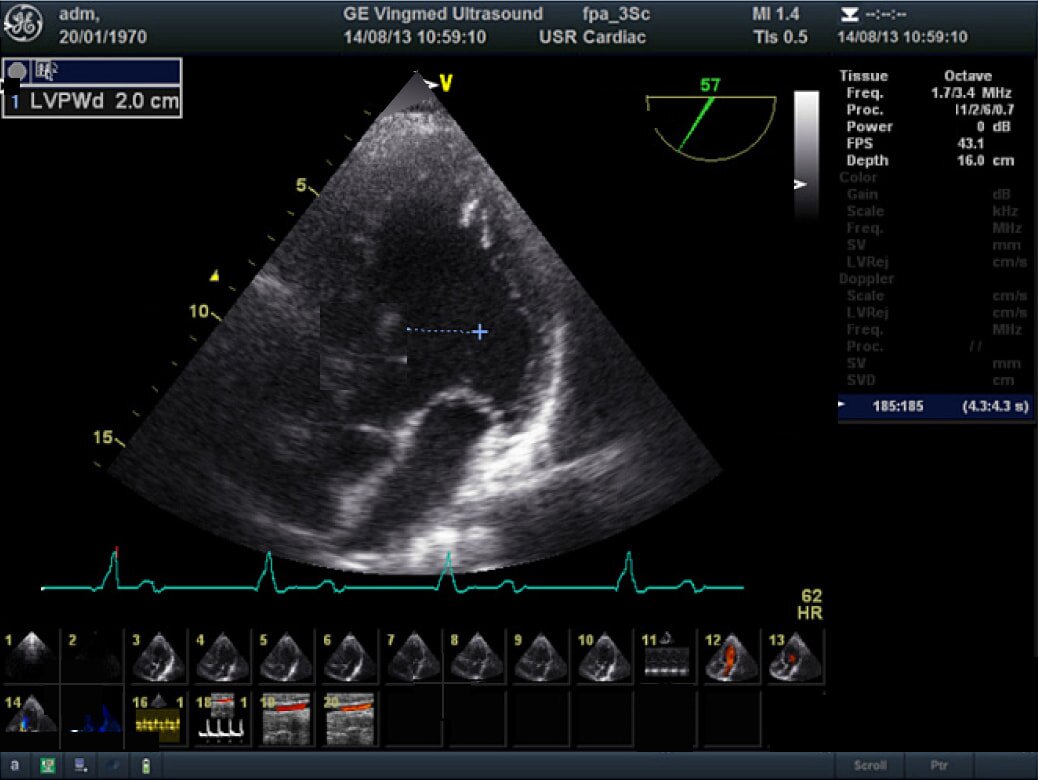

Кардиология

Если среди различных направлений диагностики в вашей клинике кардиология занимает особое место, то Vivid T8 будет прекрасным кандидатом на покупку. Ведь именно в кардиологии серия Vivid заслужила себе славу благодаря высокому качеству изображений и богатству функциональных возможностей.

Обширный набор кардиологических инструментов высокого уровня — это то, что обычно и ожидают получить пользователи, приобретая, любую из систем линейки Vivid. Новый УЗИ аппарат Vivid T8 не исключение — он оснащен широким спектром инновационных инструментов для количественной оценки, расширяющих возможности в приложениях для кардиологии:

- AutoEF (Auto Ejection Fraction) — функция автоматической недопплеровской количественной оценки глобальной сократительной функции левого желудочка с выделением зоны интереса по технологии спекл-трекинга.

- AFI (Automated Function Imaging) — автоматическое отображение функции ЛЖ — функция позволяет производить качественную и количественную недопплеровскую оценку региональной сократительной функции левого желудочка.

- 2D Auto EF 2.0 (Недопплеровская оценка объемов и фракции выброса ЛЖ)